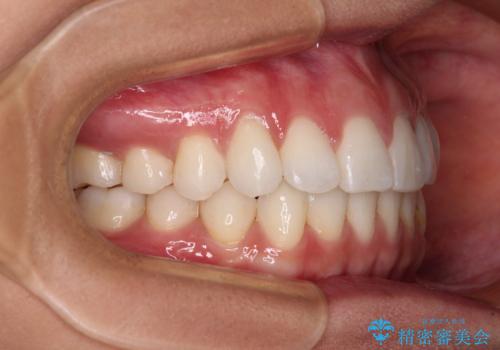

【モニター】インビザラインで口を閉じやすく

- 前に出ている上顎前歯が気になるとのことで来院された患者様です。

インビザラインを用い、IPR(歯と歯の間を削る)と歯列全体を後方に移動させることで、可能な限り前歯の突出感を改善することとしました。

元々の歯列も整っており、横顔の印象の出っ歯ではなかったため、仕上がりに満足できない可能性があると心配しておりましたが、口が閉じやすくなり、患者様には大変満足していただきました。